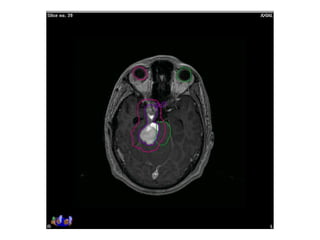

RT planning: meningioma

GTV/CTV = residual tumour / tumour bed for gr II / gr III

CTV = 5 mm for benign meningiomas

2 - 3 cms for high grade meningiomas / HPC

PTV = 2mm for SRT

5mm for 3DCRT

All normal structures contoured

Dosage:

Gr-I:

54Gy/30# conformal RT

25Gy/5# / 13Gy/1#

Gr II & III meningioma:

60Gy/30#/6wks

Conformal RT

Grade I Grade II/III

Tharmoplastic mask

CT scan with contrast- 3 mm slice

MRI scan with T1 contrast & T2 flair is a must